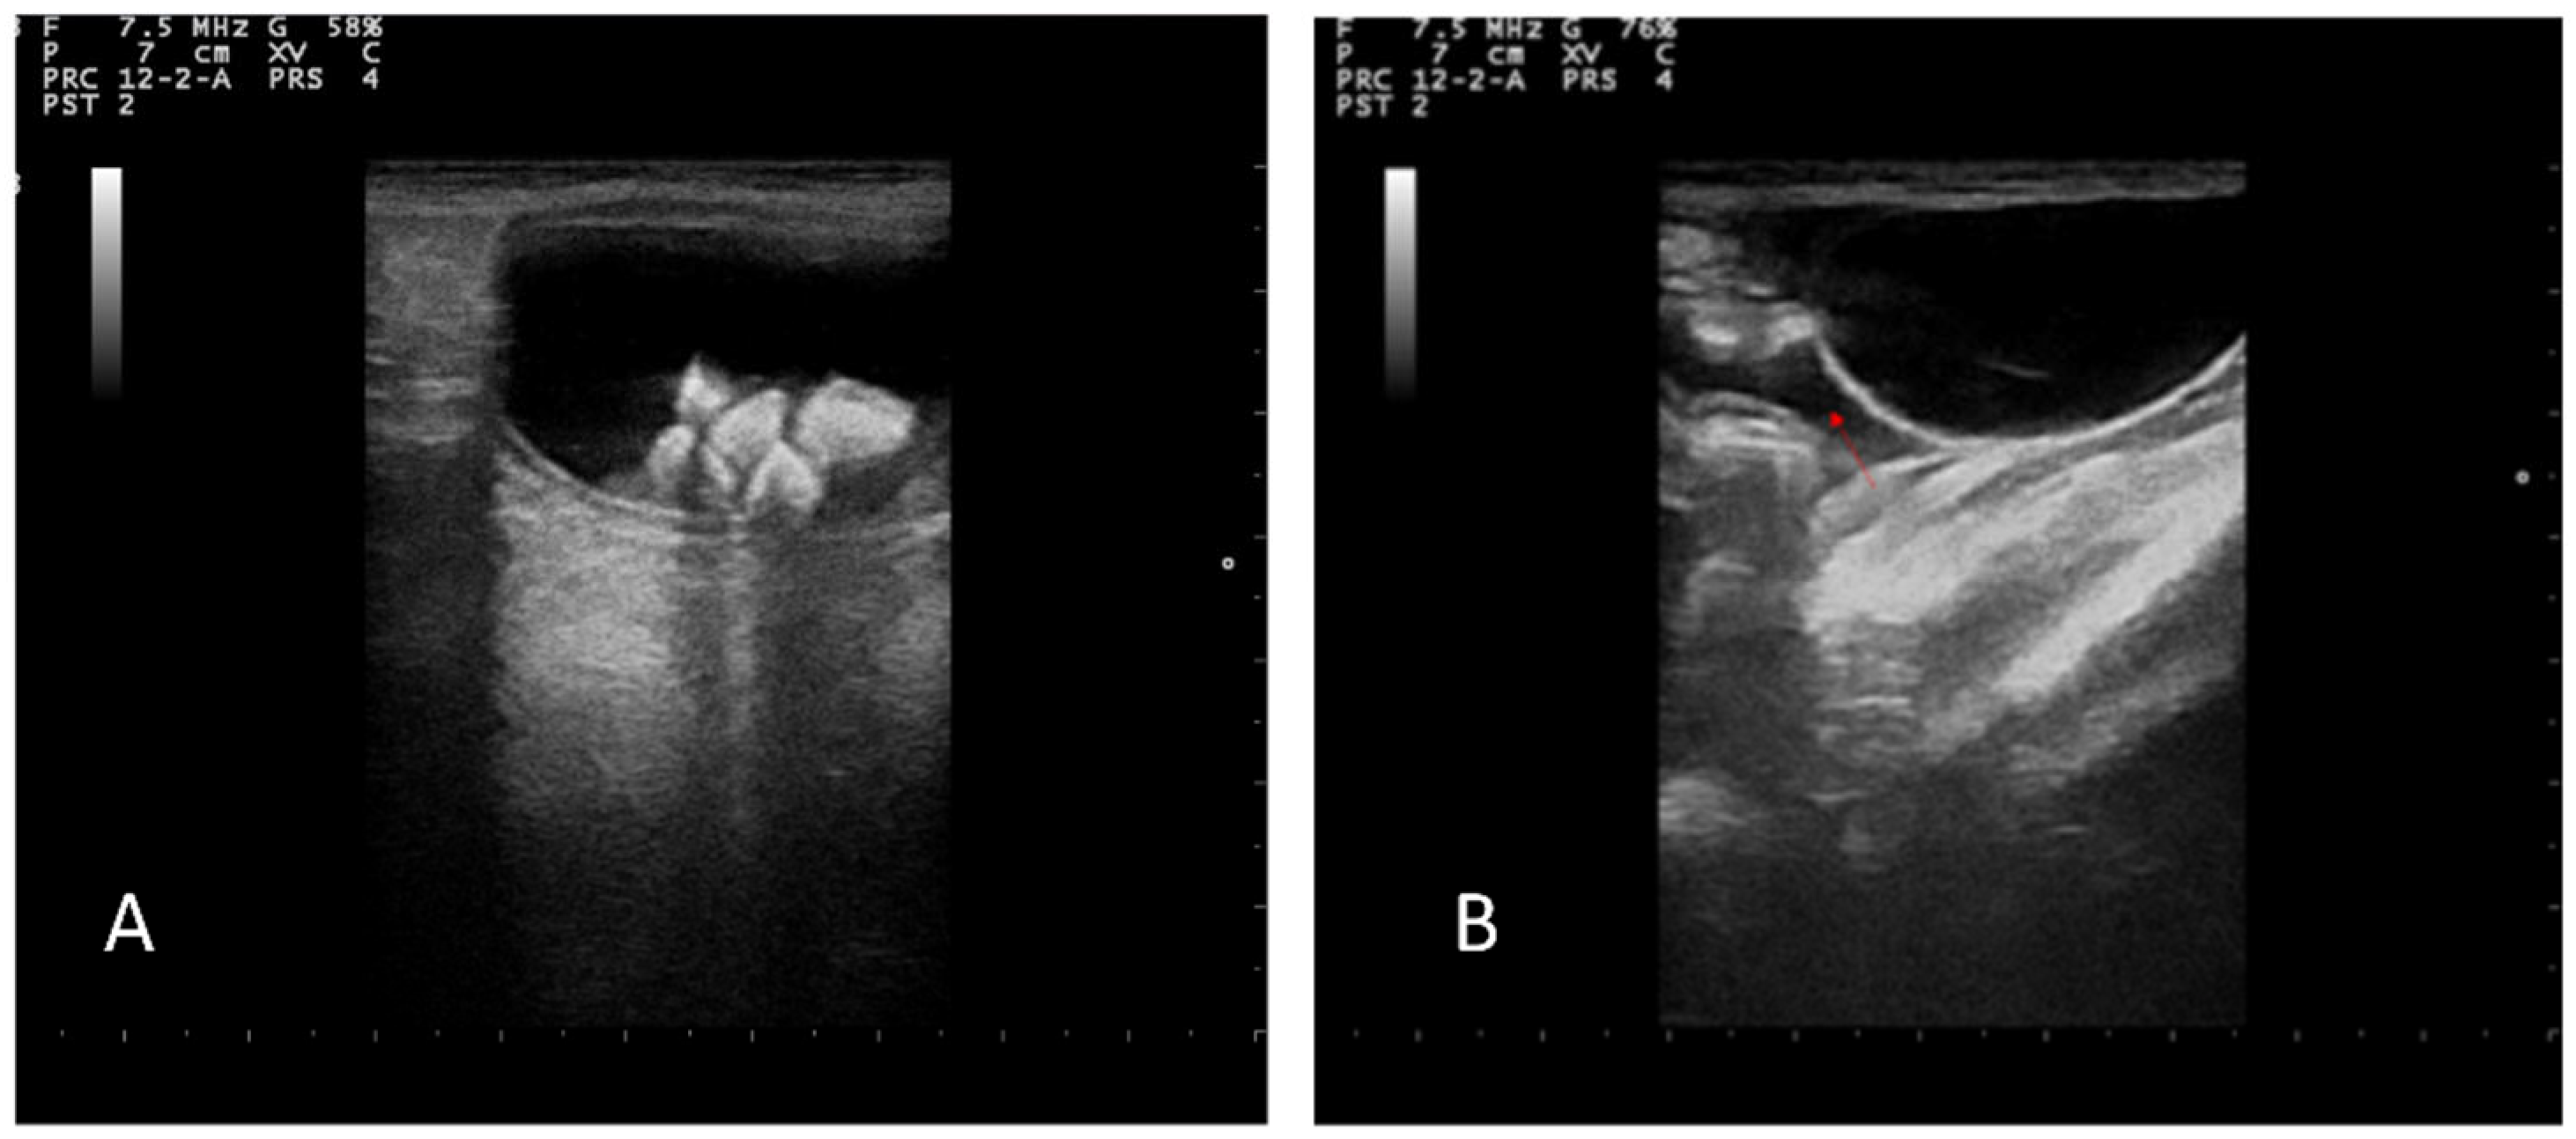

The abdominal ultrasound examination was performed using a device equipped with 5–8 MHz microconvex and 10–12 MHz linear probes (MyLab Vet 40, Esaote, Italy). Hyperechoic areas in the bladder with a posterior shadow were observed, confirming the presence of previously diagnosed uroliths; the bladder wall appeared to be intact with normal stratification. A modest amount of free fluid was observed in the peritoneum (Figure 2A,B).

Figure 2.

(A) Ultrasonographic images of urinary bladder lithiasis. (B) Free fluid in abdomen (red arrow).

Both kidneys appeared to be enlarged with a dilated pelvis (4.5 mm), preserved echo structure, and intact renal capsule. Both ureters appeared to be dilated (5.6 mm), although the entire length of the left ureter was well-visible in contrast to the contralateral (Figure 3).

Figure 3.

Ultrasound examination of the left kidney showing the dilatation of the renal pelvis and ureter (red arrow).

A large perirenal collection of anechoic fluid containing small areas of echogenic tissue attributable to intraperitoneal fat was observed in the left hemiabdomen. A capsule surrounding the lesion showed an inhomogeneous pattern with no evident stratigraphy (Figure 4).

Figure 4.

Ultrasound examination of left kidney showing anechogenic area in the left hemiabdomen (asterisk) containing small areas of echogenic tissue attributable to intraperitoneal fat.